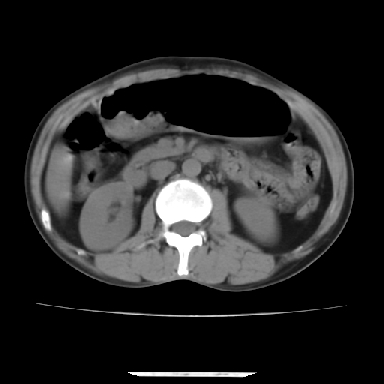

标题: CT7372:脂肪肝?外伤?

m 45 车祸,硬膜下血肿

窗宽太宽,调低点就好了,应该是不均质脂肪肝表现,请结合临床,单纯肝挫伤  其内无出血灶很少见,必要时做mri检查

窗宽太大,对比度太差了。局限性脂肪肝也有可能,但是亦不排除外伤性改变,增强扫描应该也还可以鉴别的。

肝内未见出血灶,但不能除外外伤性肝损伤,所示层面应考虑弥漫性脂肪肝.请结合临床必要时做mir检查

考虑不均匀性脂肪肝,建议增强扫描进一步检查除外合并其它病变。

肋骨无骨折,腹腔未见游离液体,所以不均匀脂肪肝首先考虑,但如果病人情况允许还是做个增强检查放心

考虑不均匀性脂肪肝,肝包膜下光整,肋骨无异常,无腹水征,不支持肝挫伤。